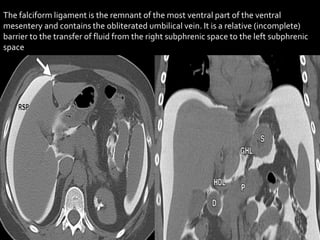

The falciform ligament is the remnant of the most ventral part of the ventral

mesentery and contains the obliterated umbilical vein. It is a relative (incomplete)

The falciform ligamentis the remnant of the most ventral part of the ventral mesentery and contains the obliterated umbilical vein. It is a relative (incomplete) barrier to the transfer of fluid from the right subphrenic space to the left subphrenic space